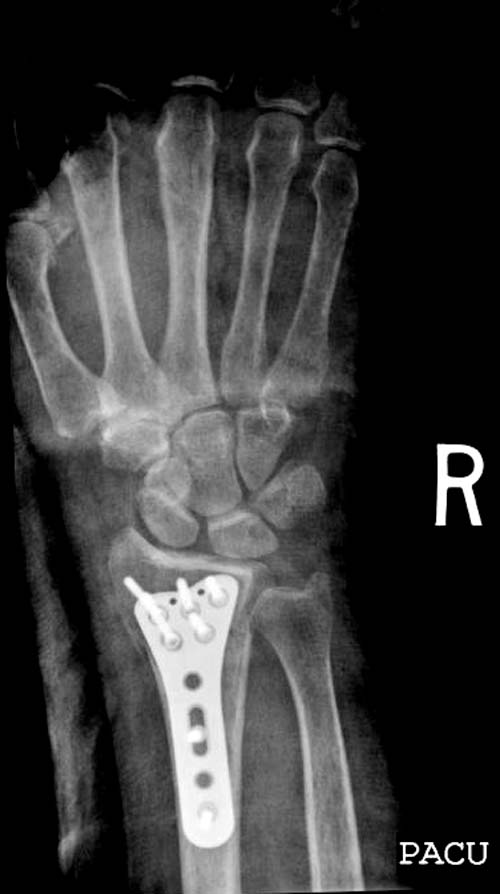

Сегодня все компании: Synthes, Stryker, Zimmer, Acumed, TriMed и т.д. имеют

пластину для фиксации дистальнего перелома лучевой кости. На снимке метод

фиксации дистальных переломов, справа Stryker, а слева пластина Synthes,

женщина 58 лет, политравма.